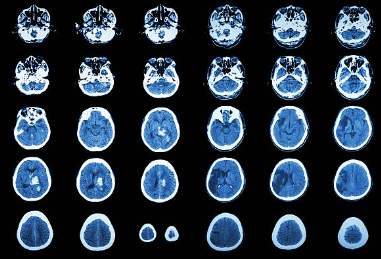

뇌경색은 뇌혈관이 막혀 혈류 공급이 차단되면서 뇌세포가 손상되는 질환으로, 뇌졸중(Stroke)의 한 유형입니다. 흔히 ‘허혈성 뇌졸중’이라고도 불리며, 조기 발견과 치료가 생명을 구하고 후유증을 최소화하는 핵심입니다.

뇌경색 초기증상은 편측 마비, 언어 장애, 시야 흐림, 갑작스러운 어지럼증, 극심한 두통 등이 있으며, 원인은 동맥경화, 심장질환, 고혈압, 당뇨, 흡연 등입니다. 조기 발견과 즉각적인 치료가 생명과 후유증을 좌우하므로, 생활습관 관리와 정기 검진을 통한 예방이 무엇보다 중요합니다.